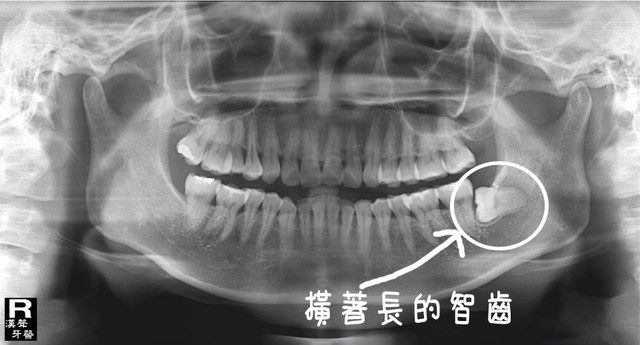

莫約三年前去看牙醫,問醫生為什麼

牙齒怪怪的?

醫生看了看,說長了

四顆智齒。

我問說要拔嗎?醫生說要拔不拔都可以。

因為是長在牙肉裡,沒有蹦出來,也沒有造成發炎,

不拔是沒有關係的。

然後很兩光的指著X光片上面的智齒,還問小護士那是什麼?

小護士瞄了我一下說:「那顆是智齒啊。」

啊我不就是要來拔那一顆的嗎?

三年前的疼痛和牙齒位置異常我完全忘光光,

這天照了X光片之後才想起來,

原來我的智齒和主人一樣很搞怪,所以橫著長…每一顆都是長橫著來的。